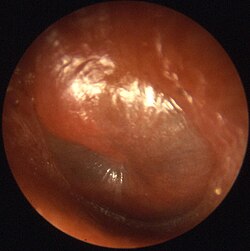

Ortaqulaq iltihablanması - otitis media. Ortaqulaq iltihablanması burun boşluğu və ya boğazdan ortaqulağa açılan kanallardan (tuba auditiva, pharyngotympanic tube) yüksələn bakteriya və ya viruslar tərəfindən iltihablanmağa səbəb olur. Ortaqulağ qulaq pərdəsi ilə iç qulaq arasında içi hava dolu olan bir orqandır. Nadir olaraq da qulaq pərdəsinin cırılması nəticəsi, buradan bakteriya və viruslar içəri girərək iltihablanmağa səbəb ola bilər. Ortaqulağ iltihablanması böyük ağrı və irinlənmələrin axışına səbəb olur. Əgər iltihablar, qulaq pərdəsinin arxasında toplanib sərtləşsə eşitmənin keyfiyyəti aşağı düşər və ağrıdan insan yata bilməz. Burada sərtləşən iltihablar qulaq pərdəsini deşər və burdan iltihablar çölə axar.